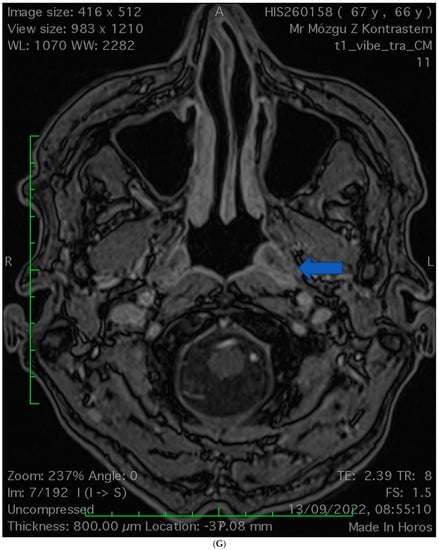

2.2. Case 2